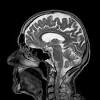

Scans reveal the brain's early growth, late decline and surprising variability The ongoing study could eventually lead to brain growth charts that would allow doctors to look for signs of atypical development in young patients. But for now, the results are meant for scientists who study typical brain growth or brain disorders like ...

Brain charts map the size of the human brain over a lifetime Researchers found a way to track the size of the human brain over a person's lifetime, allowing them to compare brain growth and decline in a manner similar to how pediatricians use growth charts to measure a child's development.